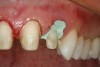

Figure 15  After removal of the defective restoration, it can be seen clinically that the margin of the preparation on the distal of tooth No. 21 was extremely subgingival. The surrounding periodontium was inflamed and hemorrhagic. The laser was used to perform apical repositioning of the bony crest using a closed-flap technique.

Figure 15